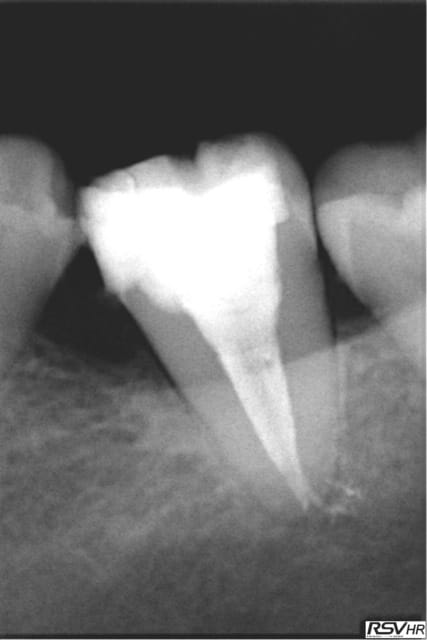

Ce sont des cones dentsply mais pas les réciprocs. je les scelle au tubuli seal en pompant un peu ( d'ailleurs sur la 25 ci dessous qui avait un 4eme ca a fait un dépassement preuve que ca fuse) je les coupe ensuite au système B avec le pluggeur qui sert à faire le bouchon apical.

Tres pratique d'ailleurs pour faire le cas échéant les tenons dans la séance de l'endo, l'empreinte et la provisoire dans la foulée.

R1 yd7c5a - Eugenol

R2 rn8qyd - Eugenol

R2 ts2qmh - Eugenol

Tu as fait des progrès. Disons par exemple que sur la deuxième prémolaire, tu es allé un poil trop loin, ce qui a réduit sérieusement la constriction apicale. Peut être que que tu mesures ta LT un demi millimètre plus longue que nécessaire.